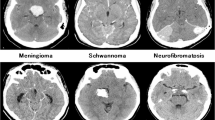

Brain tumors accurate classification and early detection are important for prognosis assessment, treatment planning, and surgical decision-making. Brain tumors, including meningiomas, gliomas, and pituitary tumors, vary in their aggressiveness, growth rates, and imaging characteristics. Meningiomas appear as well-circumscribed, extra-axial masses, whereas Gliomas, are heterogeneous and infiltrative on MRI. To improve clinical outcomes, understanding these distinctions is vital. Automated detection systems assist radiologists and enhance clinical workflow efficiency by offering preliminary assessments, aiding early diagnosis, and reducing human error.